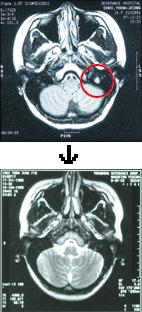

±¸°æÈ¸ Áý»ç(¿µ»ê±³È¸)

³úÁ¾¾ç Ä¡·áÇϽŠ¿ÏÀüÇÑ Çϳª´Ô ´É·Â¾È¸é¸¶ºñ ¡¤ û·Â»ó½Ç °íħ ¹ÞÀº ±âÀû ¡°¾ö¸¶, ¿ÞÂÊ »´ÀÌ ÀÌ»óÇØ¿ä¡±97³â 11¿ù ÃÊ ÁßÇб³ 3ÇгâÀÌ´ø µþ ¾ÆÀ̰¡ »´ÀÌ ±»¾îÁ³´Ù¸ç ¿ï»óÀ» Áö¾ú´Ù..... ¤Ó2002-08-23